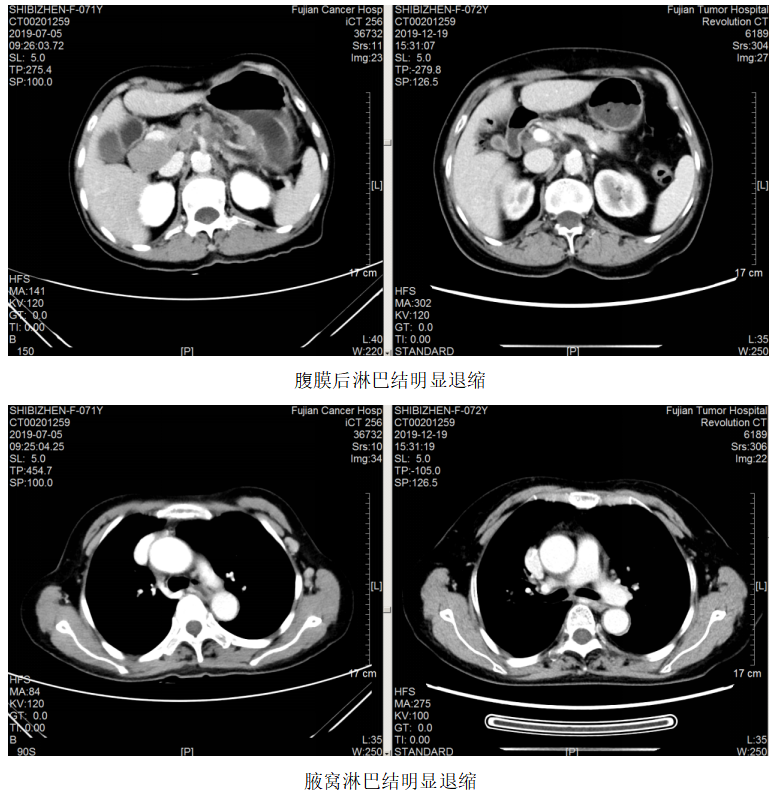

图1.2019.7.5影像(基线评估)

一线治疗:2019.7.12~10.24予FOLFOX方案(奥沙利铂110mg+左亚叶酸钙300mg+5-Fu 2.75)化疗8周期,曲妥珠单抗220mg靶向治疗7次。

局部放疗:2019.7.23~2019.8.7予脑转移灶调强放疗DT3900CGy/13F。

疗效评估:PR。